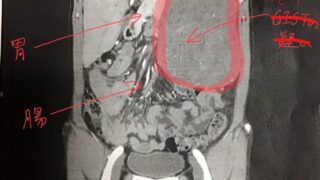

手術から7.0年が経過した。半年ごとの定期検査ですが、今回は腹腔内デスモイドの件があるので心配。腹腔内デスモイドの発見と手術悪性転化しやすい腫瘍の種類(びまん性星細胞腫グレード2)であるとのことで造影剤を注射してMRI検査をする。4時間前か...

2)デスモイド腹腔内腫瘍

DESMOID:腹腔内デスモイドの治療と経過・・・脳腫瘍との比較!

稀な腫瘍であるデスモイド腫瘍がおなかの中に見つかって手術したので、誰かの参考になればと思って記録しておく。過去には稀な腫瘍の一つである脳腫瘍のグリオーマも経験しているので、おなかと頭の場合を比較する形で記載してみた。ちなみにグリオーマは50...